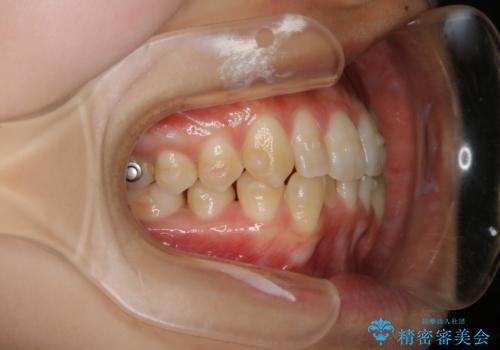

- 上の前歯が1本後ろに入ってしまっていることが気になるとご相談にいらした方です。

元々下の前歯が1本欠損しており、上下の噛み合わせや、歯のサイズバランスを考慮しながら治療を行いました。

クロスバイトしている歯が深く噛み込んでおり、この歯を外に出してくる際に強い咬合力が加わると歯が失活する恐れがあることを説明し、合わせて咬筋へのボトックス注入を行いました。

下顎切歯が1本欠損しているため、上顎前歯部を少しずつストリッピングして、上下の噛み合わせ、バランスの向上を図りました。